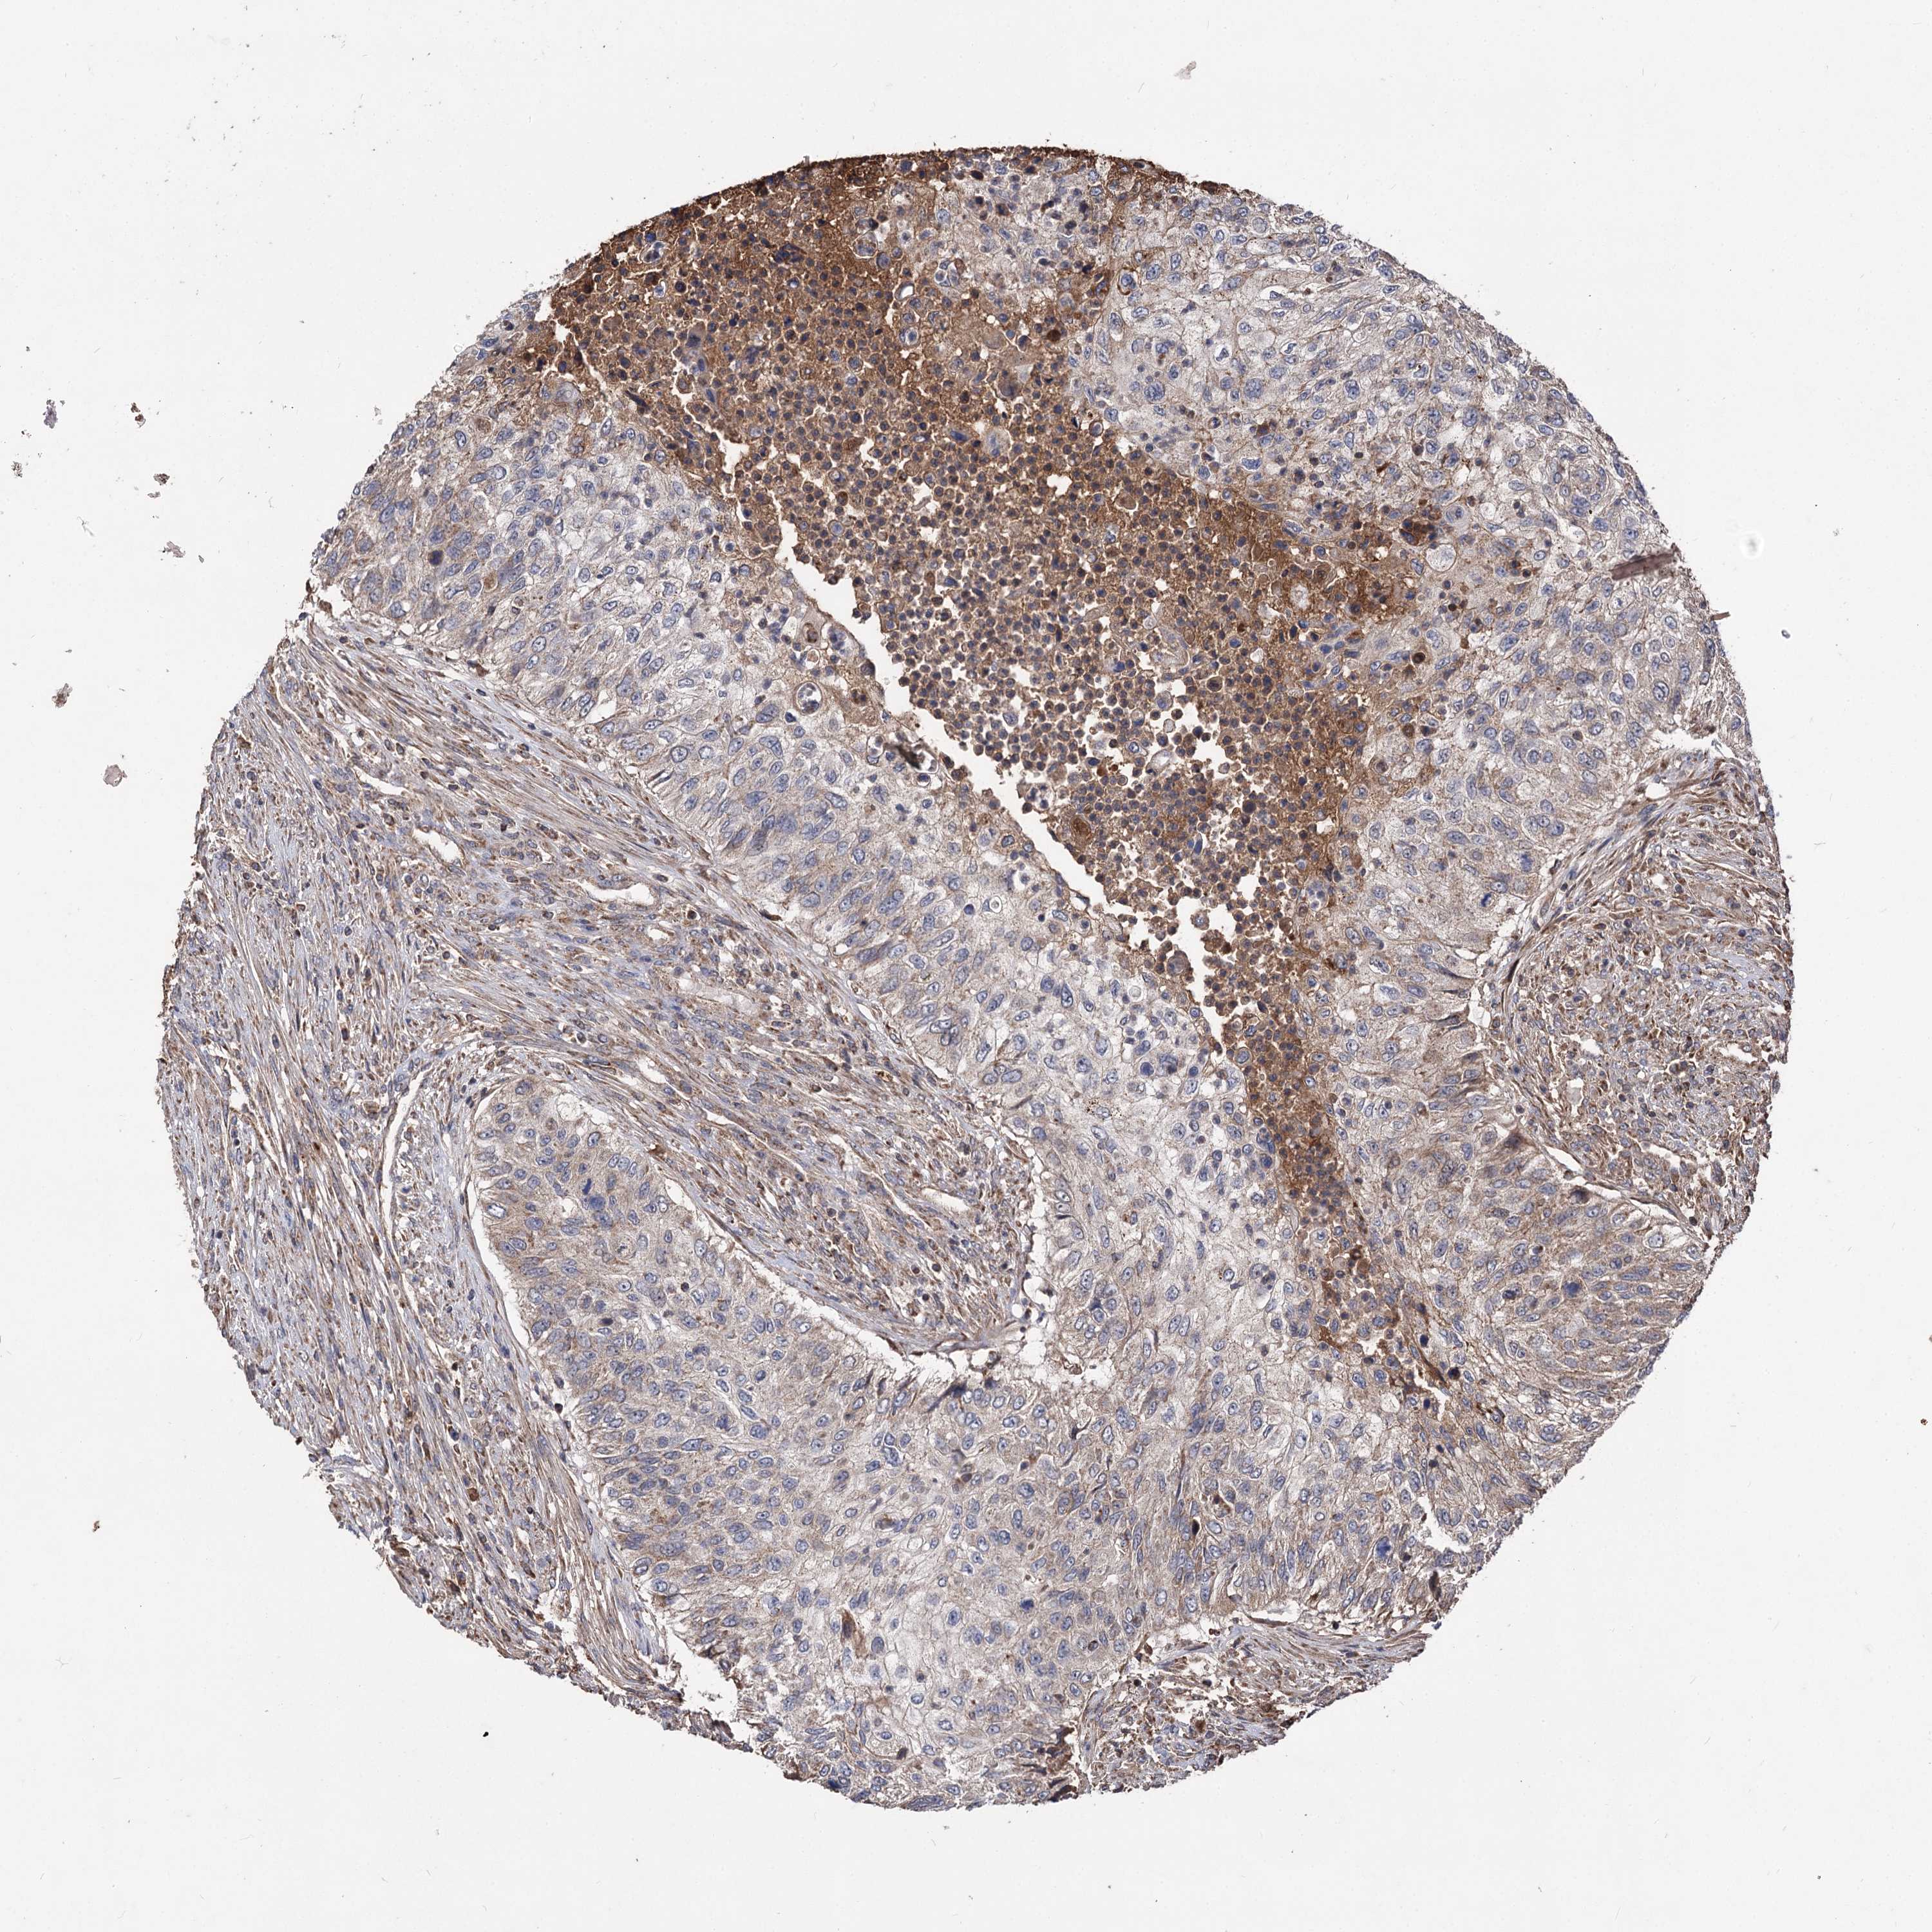

UROTHELIAL CANCER - Protein expressioni

A mouse-over function shows sample information and annotation data. Click on an image to view it in a full screen mode. Samples can be filtered based on level of antibody staining by selecting one or several of the following categories: high, medium, low and not detected. The assay and annotation is described here.

Note that samples used for immunohistochemistry by the Human Protein Atlas do not correspond to samples in the TCGA dataset.

Antibody stainingi

Antibody staining in the annotated cell types in the current human tissue is reported as not detected, low, medium, or high, based on conventional immunohistochemistry profiling in selected tissues. This score is based on the combination of the staining intensity and fraction of stained cells.

Each image is clickable and will lead to virtual microscopy that enables deeper exploration of all samples and also displays staining intensity scores, fraction scores and subcellular localization as well as patient and tissue information for each sample.

Antibody HPA038469

Antibody CAB022664

Antibody CAB034035

Staining

High

Medium

Low

Not detected

Intensity

Strong

Moderate

Weak

Negative

Quantity

>75%

75%-25%

<25%

None

Location

Nuclear

Cytoplasmic/membranous

Cytoplasmic/membranous,nuclear

Urothelial carcinoma, High grade

Urothelial carcinoma, Low grade